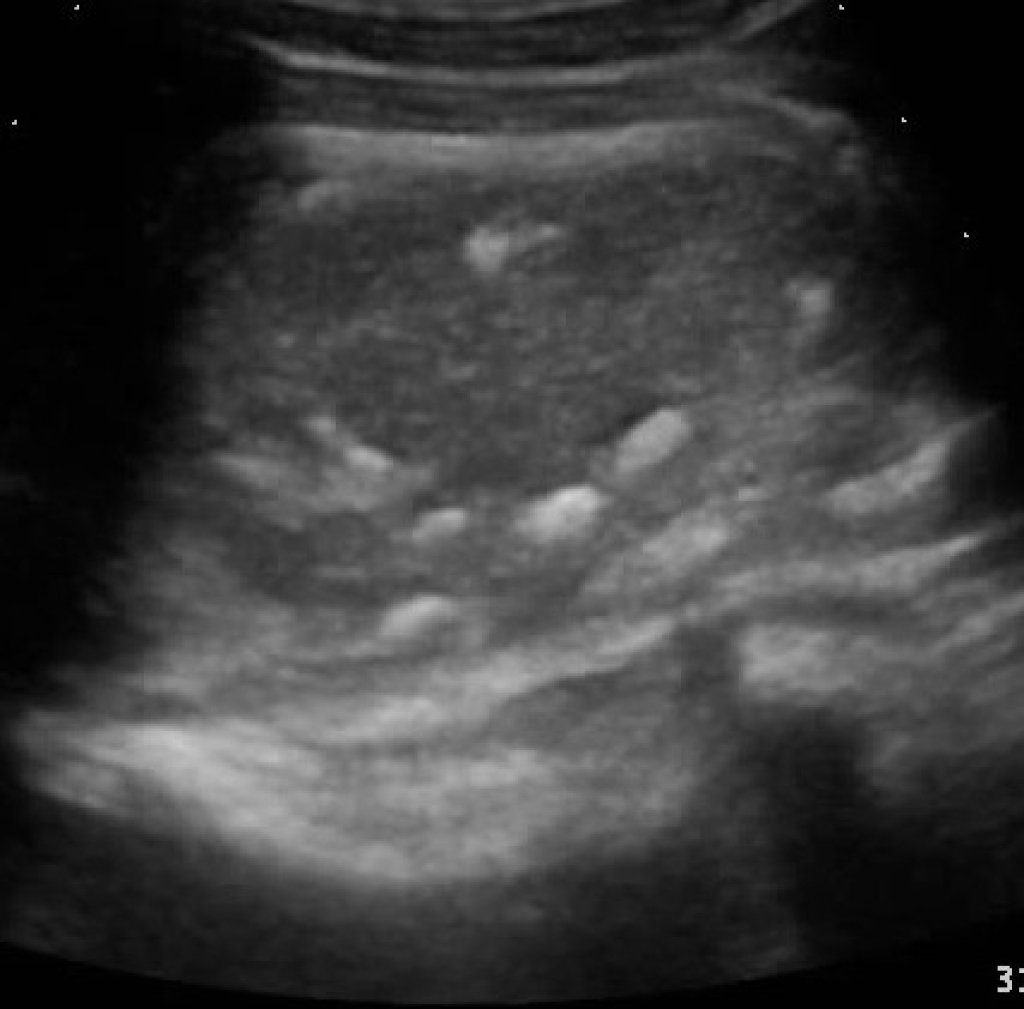

Rechts: Echobeeld: slijmbeursontsteking met mineralisaties

Echobeeld: slijmbeursontsteking met mineralisaties